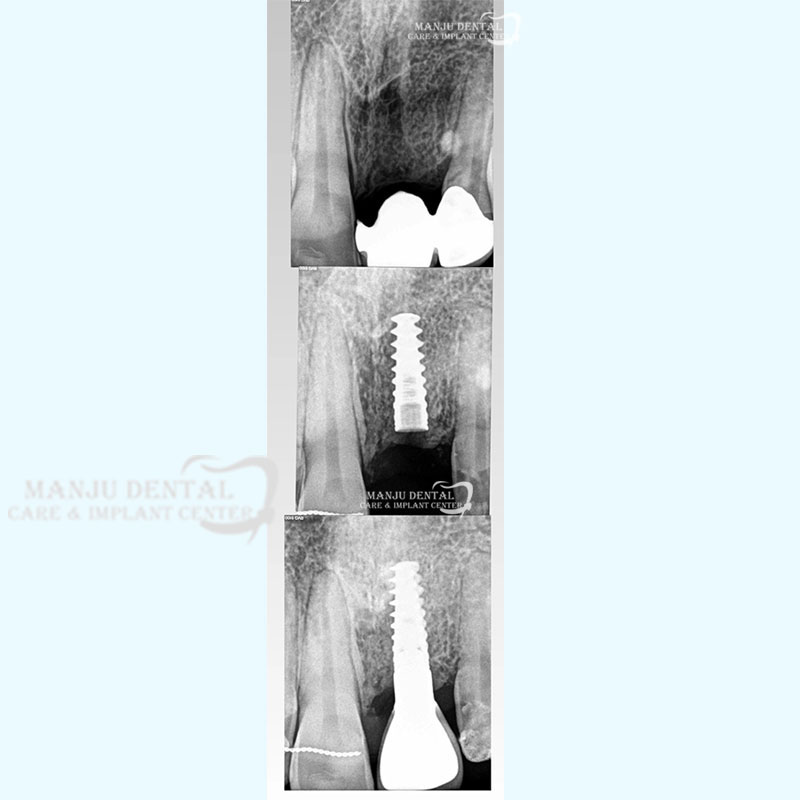

Dental implant the gold standard for tooth replacement

Osteointegrated implant achieving perfect function and form